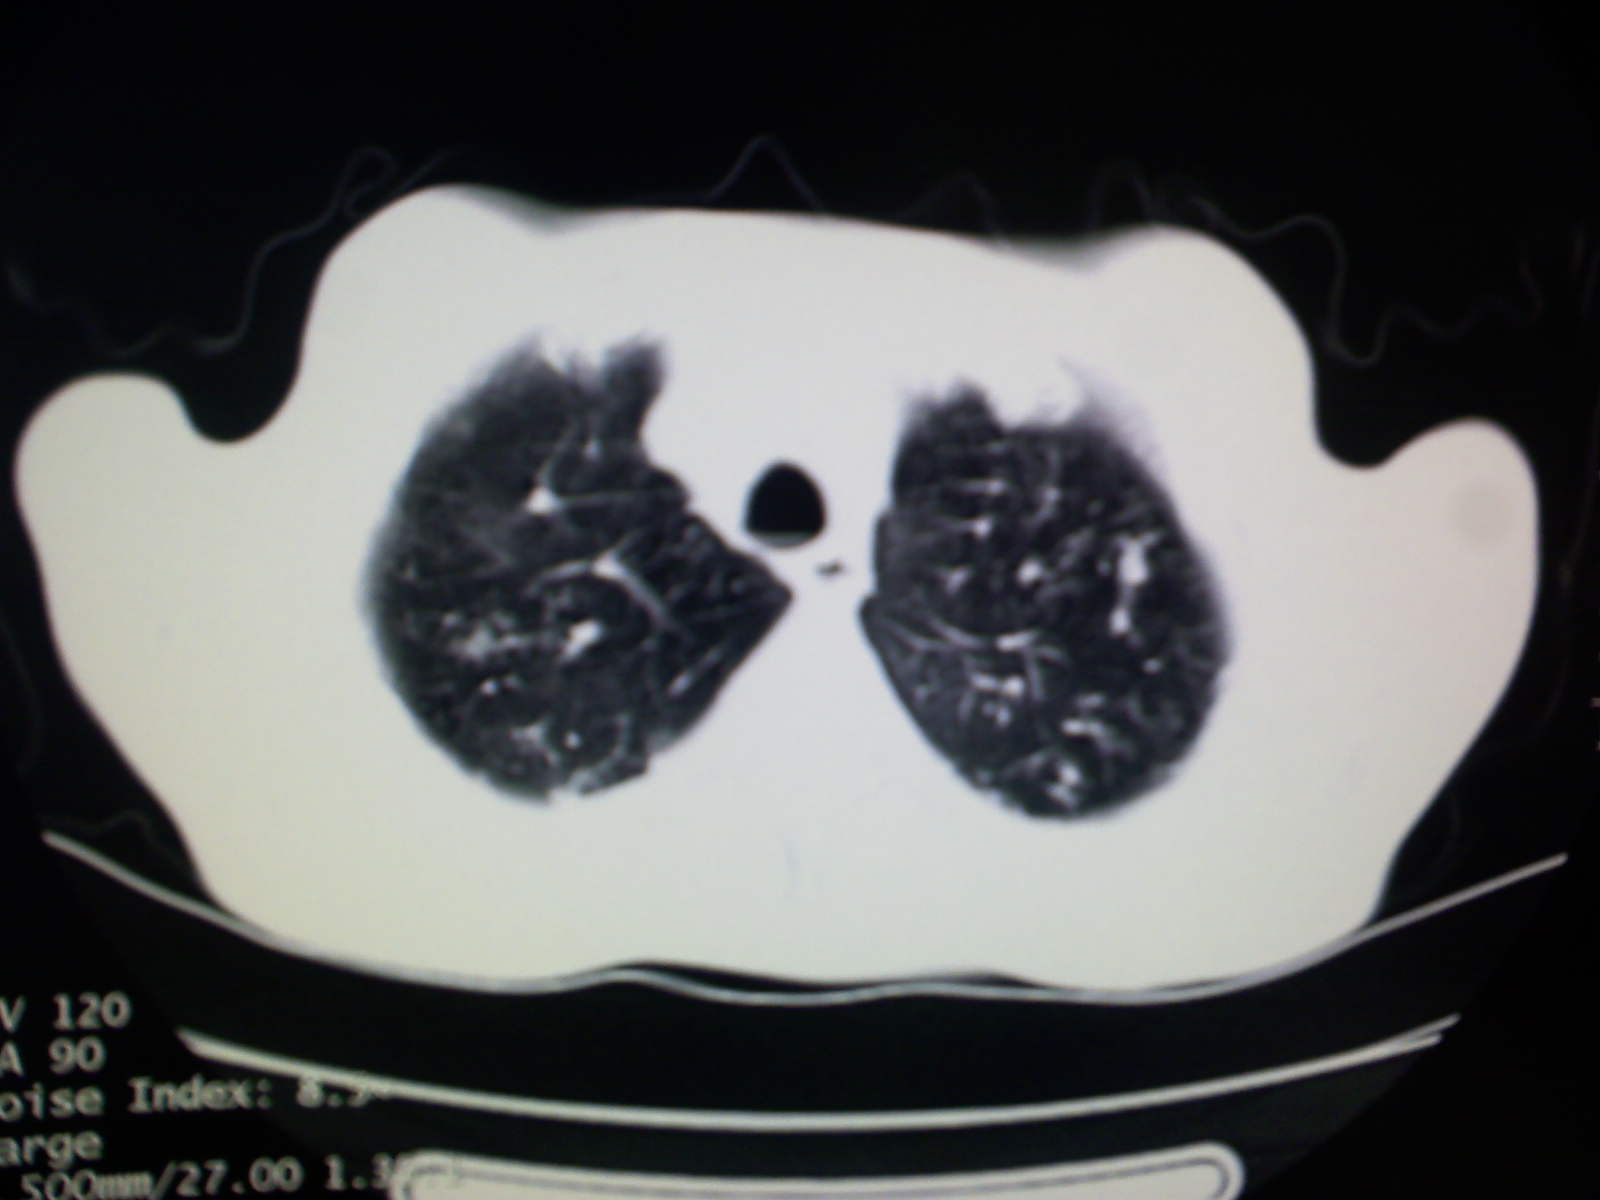

以下是引用卜一在2009-4-11 15:50:00的发言:[br]双肺继发性肺结核伴空洞形成,不排除合并霉菌感染!(病灶呈多形态 多特征 散在分布)。另:合并支气管扩张征伴感染!

以下是引用主力军在2009-4-11 15:55:00的发言:[br]两肺继发性肺结核可能性大。

以下是引用康鹏在2009-4-11 16:30:00的发言:[br]双肺继发性肺结核伴空洞形成合并感染[br]支气管扩张合并感染